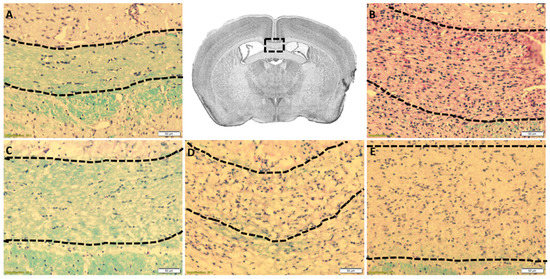

The cuprizone intoxication model consistently shows demyelination in the CC beginning at week 3.5 and ending in full demyelination by week 5.0, most consistently at the level of the fornix. Figure 2A shows control mice not exposed to Cuprizone, revealing fully myelinated (blue stained fibers) within the CC, whereas mice exposed for 5 weeks were fully demyelinated, showing negligible amounts of myelin (Figure 2B). Furthermore, mice not exposed to cuprizone showed no detrimental effect on normal myelinated CC. Importantly, mice exposed to cuprizone for 3.5 week (faint amount of blue-stained fibers) demonstrate partial demyelination (Figure 2D,E), while full demyelination is noted post 5.0 weeks of CF as well as increased cellularity from MM (Figure 2B). These data suggest the induction of demyelination occurred as predicted and suggest the 18F-PBR-111 had no obvious detrimental effects on a myelinated CC. The results imply that sterile inflammation manifested by MM accumulation is present in CF mice.

Figure 2. Cuprizone-induced demyelination of the corpus callosum in 18F-PBR-111 injected mouse brain sections. Representative image in the first row, center box, demonstrates the area of analysis. LFB-PAS staining of control (A) and 18F-PBR-111 injected (BE) mice after 0 (A,C), 3.5 (D,E), and 5 weeks (B) after cuprizone treatment was used to analyze myelin levels (blue) and cellularity from MM (dark purple nuclei). Hand-drawn dotted lines represent the area in which scoring for myelin and cellularity was conducted. White scale bar represents 50 microns.